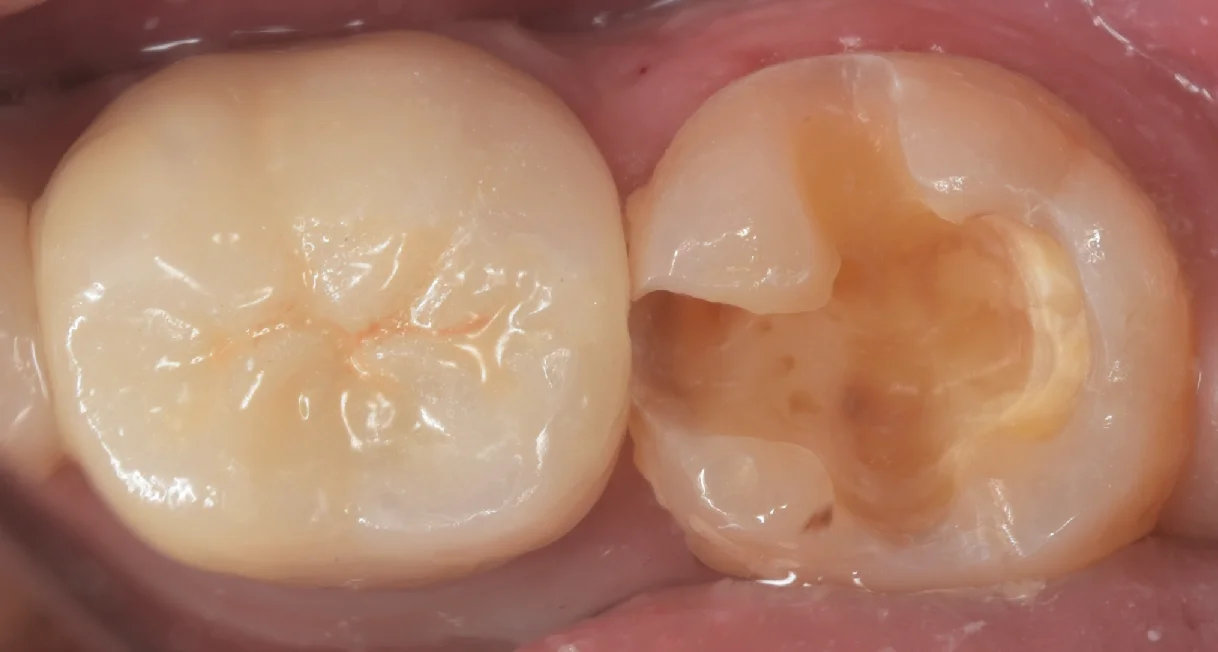

古い詰め物を除去し切ったのがこちらになります。

詰め物の精度を確保するためにはどうしても健康な歯の部分を削ることになりますので、術前の状態よりも多少大きく削られている状態になっています。